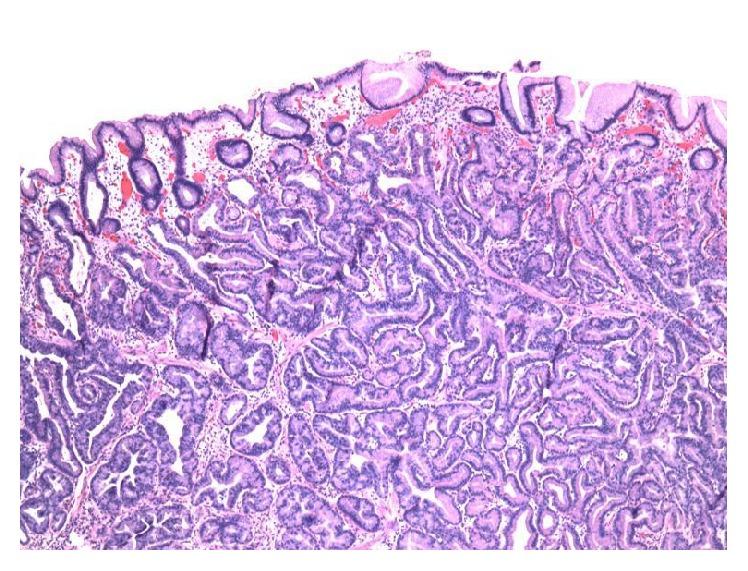

Gastric adenocarcinoma of the fundic gland type (GA-FG) is a rare entity that has only recently been described and defined. There is ongoing controversy regarding the malignant potential of this lesion. We report the case of a GA-FG in a 49-year-old Caucasian man who was referred to endoscopy for management of an incidentally found gastric polyp. Endoscopy showed a single polypoid lesion in the gastric fundus which was successfully removed with endoscopic resection. Grossly, the polyp measured 1.1 cm in greatest dimension. Microscopic examination showed irregularly branched neoplastic glands covered with a nonneoplastic foveolar epithelium. The continuity between the neoplastic glands and the fundic glands is clearly identified, indicating the tumor arose from the fundic glands. The tumor cells exhibited occasional oxyntic cytoplasm with enlarged atypical nuclei. The tumor invaded the submucosa with complete disruption of the muscularis mucosae and mild lymphocytic and fibroblastic stromal reaction. No necrosis, mitosis, or lymph-vascular invasion was identified. Although some authors have proposed reclassification of GA-FGs as oxyntic gland polyps/adenomas, in light of several reported cases with submucosal invasion as well as lymphatic invasion, we maintain that this neoplasm is best categorized as an extremely well-differentiated adenocarcinoma to reflect its invasive potential.

胃底腺型胃癌(GA - FG)是一种罕见的疾病,直到最近才被描述和定义。关于这种病变的恶性潜能存在持续的争议。我们报告了一例49岁白种男性的GA - FG病例,该患者因偶然发现的胃息肉接受内镜检查。内镜检查显示胃底有一个单个息肉样病变,通过内镜切除成功切除。大体上,息肉最大直径为1.1厘米。显微镜检查显示有不规则分支的肿瘤性腺体,表面覆盖非肿瘤性的小凹上皮。肿瘤性腺体与胃底腺之间的连续性清晰可辨,表明肿瘤起源于胃底腺。肿瘤细胞偶尔可见壁细胞样细胞质,核增大且异型。肿瘤侵犯黏膜下层,黏膜肌层完全破坏,伴有轻度淋巴细胞和纤维母细胞性间质反应。未发现坏死、核分裂或淋巴血管侵犯。尽管一些作者提议将GA - FG重新分类为壁细胞性腺息肉/腺瘤,但鉴于有几例报告显示存在黏膜下侵犯以及淋巴侵犯,我们认为这种肿瘤最好归类为高分化腺癌,以反映其侵袭潜能。